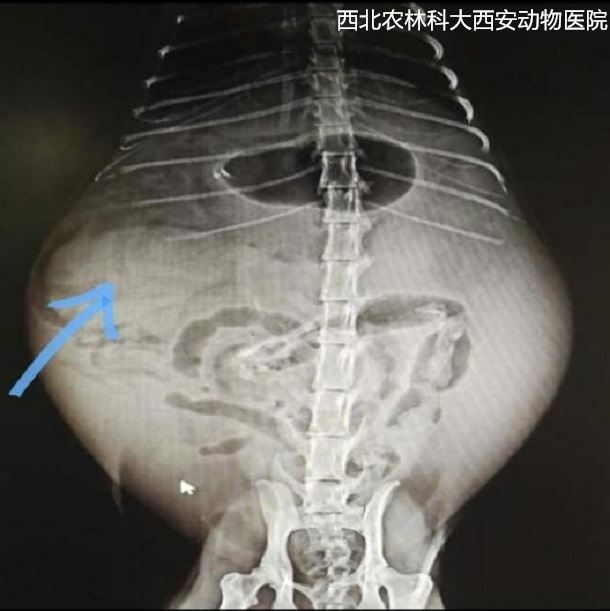

輔助檢查:腹部平片顯示腹腔有一中等密度占位性病變位于左下腹部,腹部器官邊緣銳利程度消失,腹部影像漿膜細節(jié)不能清晰可見,胃和部分腸管積氣,提示腹腔積液、疑似占位待查見(圖1)。為進一步診斷腹部占位的性質,對患寵進行了超聲檢查,結果顯示腹腔間隙無回聲,腸管游離,腹腔肝后至膀胱有一非均質、低回聲腫物,邊緣圓鈍,輪廓清晰,腫物內部偶見低回聲病灶。提示腹腔積液、脾腫大且結構異常,未見扭轉,待查見(圖2)。

圖一